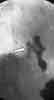

Figure 2

Two days later, the patient againcomplained of epigastric pain and experiencedatrial fibrillation. Becauseof her recent airplane trip, a spiralCT scan of the thorax was obtained toassess for pulmonary embolism. Thestudy demonstrated mediastinal airposterior to the esophagus (Figure 1)and a possible distal esophageal perforation,which was confirmed by ameglumine diatrizoate esophagramthat revealed extravasation of the contrastconfined to the mediastinum(Figure 2).